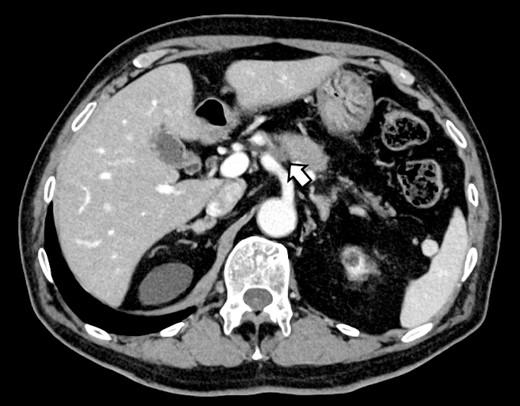

(A, B) CT on postoperative Day 56. Contrast-enhanced CT shows a pseudoaneurysm at junction of the GDA and PHA (arrow).

Subsequently, interventional radiology (IVR) was performed. However, because the inferior pancreaticoduodenal artery (IPDA) was very narrow, the microcatheter could not be followed, and hemostasis with IVR was difficult. Therefore, on POD 48, relaparotomy pseudoaneurysm repair was performed. The abdomen was opened through an inverted L-shaped incision, and adhesiolysis was performed, after which a pseudoaneurysm was revealed at the junction of the GDA and PHA. Four transfixing sutures with 3–0 prolene were used. After confirming that the liver blood flow was maintained, surgery was completed. However, bloody drainage from the drain was observed on POD 56. CeCT revealed a pseudoaneurysm (Fig. 3A and B). IVR was considered difficult because of the narrow blood vessels; therefore, the patient underwent a second laparotomy for hemostasis. A pseudoaneurysm was further observed at the junction between the GDA and PHA. In this operation, we used deeper and wider penetrating sutures than in the previous surgery to completely halt blood flow in the GDA. We confirmed that the blood flow to the liver was maintained; however, it was deemed weak. The patient had an uneventful postoperative course without bleeding, and CeCT performed on POD 61 confirmed the disappearance of the pseudoaneurysm. Although the blood flow in the PHA could not be confirmed, the right and left hepatic arteries were preserved (Fig. 4). On POD 76, CT revealed no liver abscesses or infarctions. The drain was removed on POD 78, and the patient was finally discharged on POD 107 without rebleeding or liver failure.